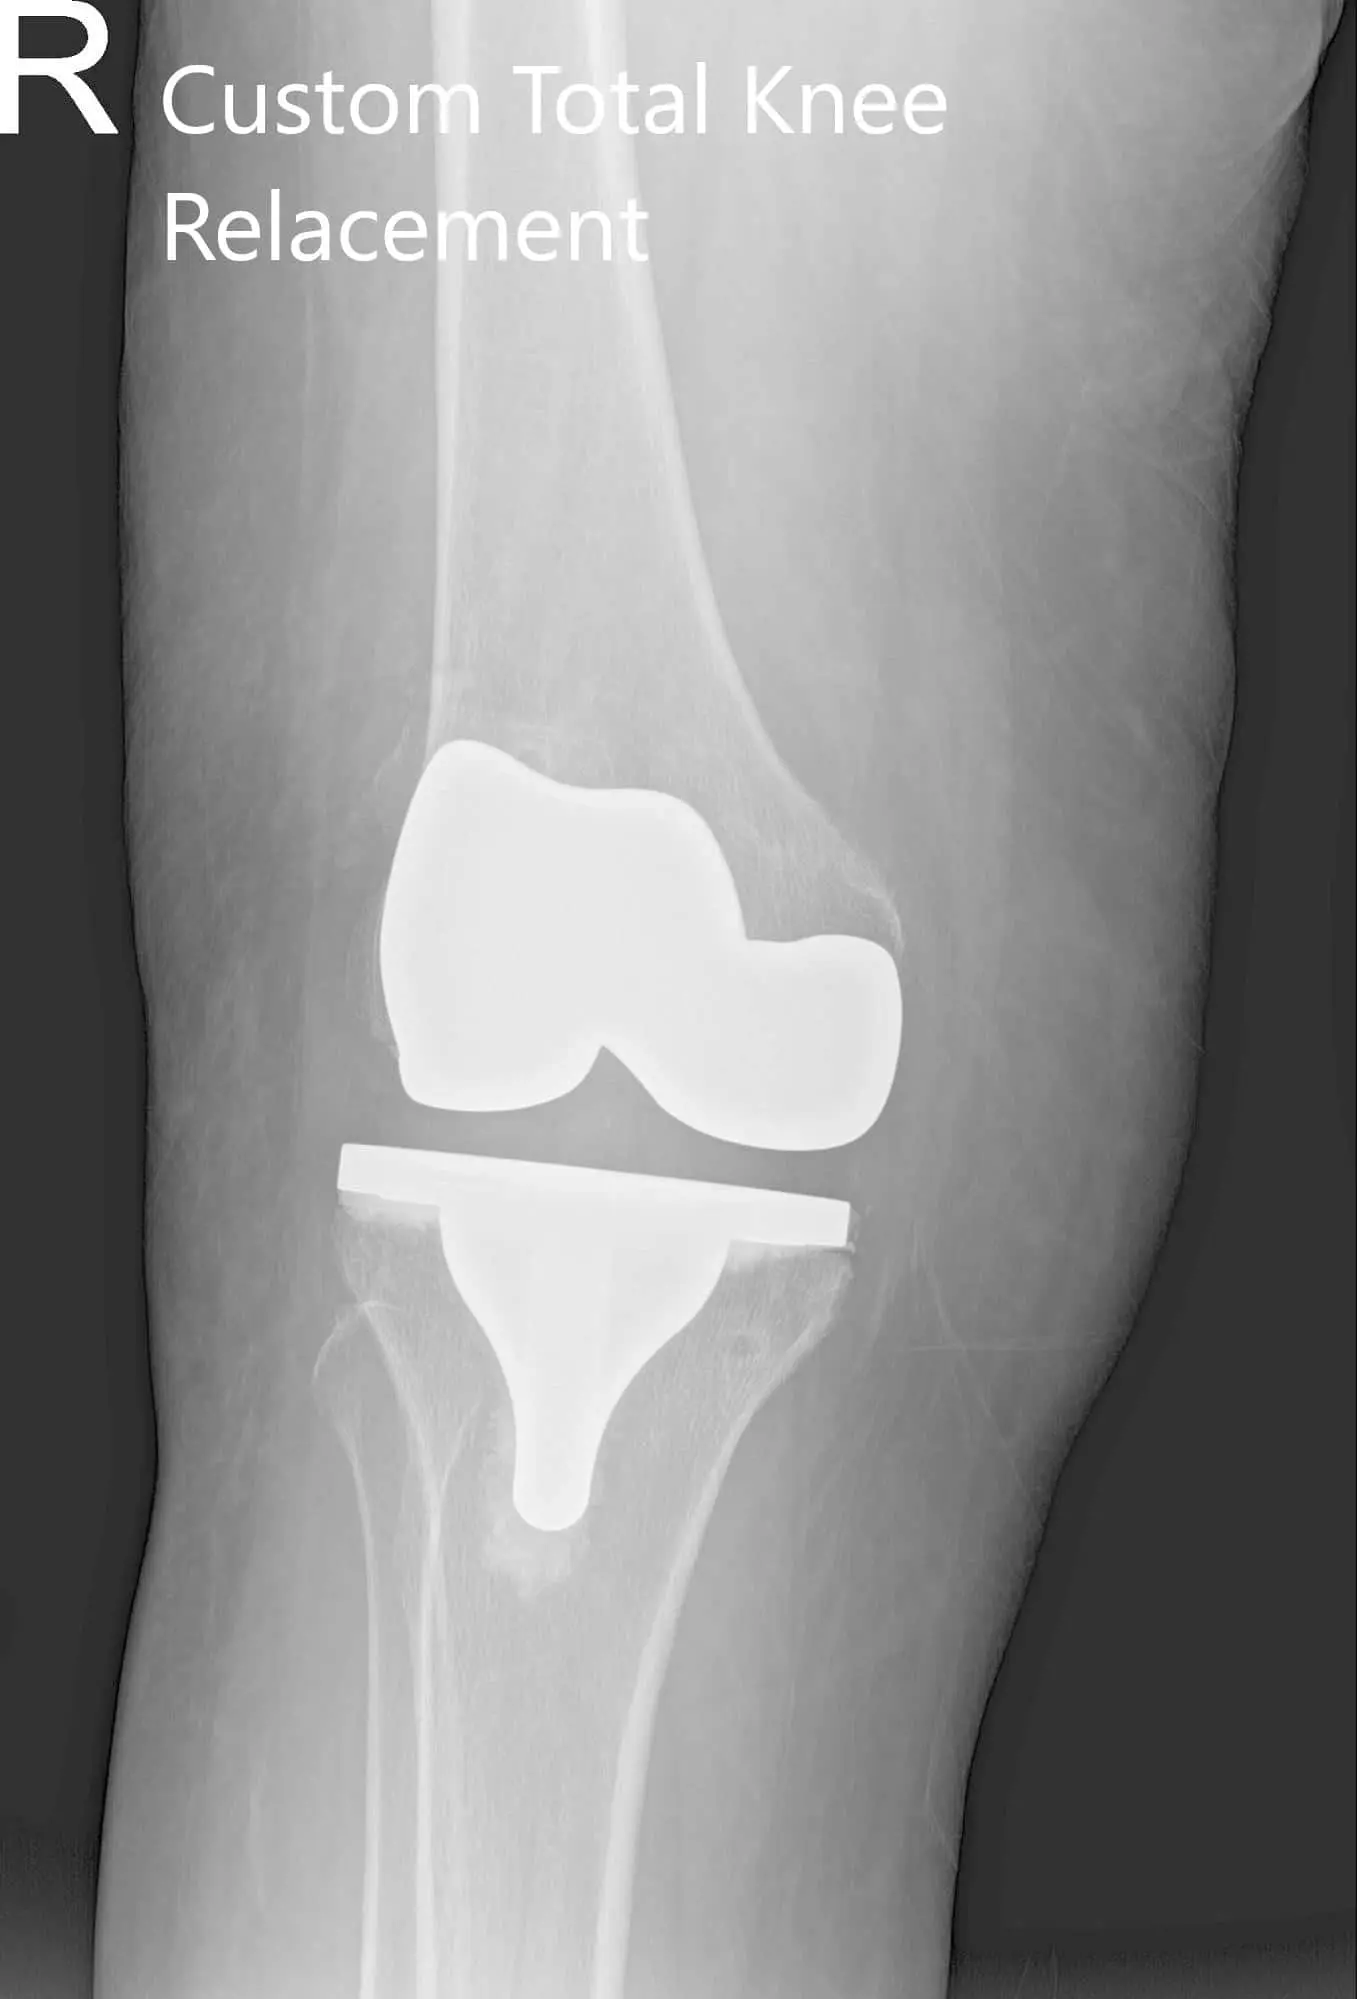

IMPLANTS USED: Custom femur and tibia bilaterally, with 10 mm polyethylene bilaterally. Right 29 mm x 6 mm patella and left 32 mm x 6 mm patella.

Postoperative X-ray showing AP and lateral views of the right and the left knee joint